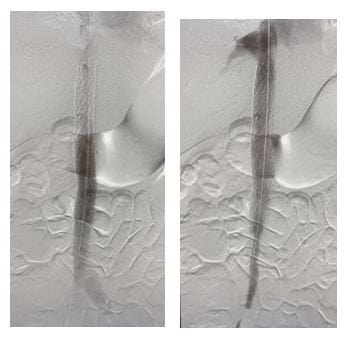

To address the problem, Dr. Harth performed a staged complete IVC and bilateral iliofemoral thrombectomy and recanalization. In addition, she reconstructed the patient’s congenitally occluded retro-hepatic IVC with IVC stenting.

“Repeat mechanical thrombectomy with a larger device of the residual thrombus allowed us to remove more of the chronic, sub-acute thrombus that we couldn’t remove with suction thrombectomy,” Dr. Harth says. “We then proceeded to dilate up her retro-hepatic IVC which originally started off as an occluded vessel, to a 20 mm diameter with intravascular ultrasound and venographic guidance and ultimately deployed a 20 mm stent.”